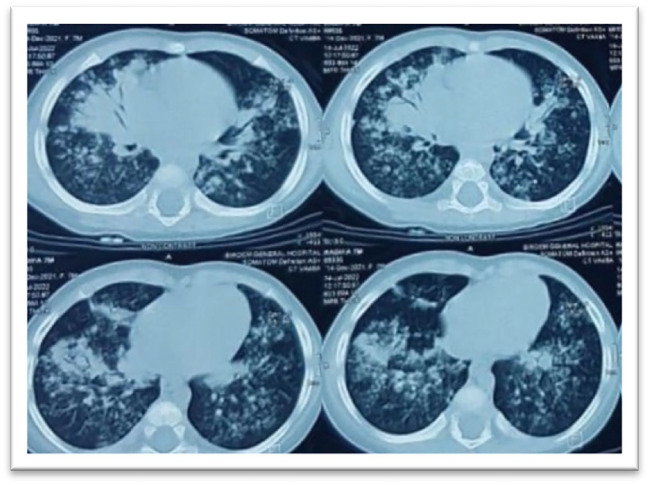

A 7-month-old girl had been suffering from progressively deteriorating pneumonia despite getting multiple courses of broad-spectrum antibiotics as well as anti-fungal drugs for adequate duration. To find out the cause behind this deterioration, the patient underwent thorough clinical and relevant laboratory evaluation including chest radiology & imaging, screening for primary immune deficiency disorders (PID), cystic fibrosis, tuberculosis, invasive fungal pneumonia, congenital heart disease, covid pneumonia, TORCH etc. but failed to solve the mystery. Upon further detailed re-evaluation, it was discovered that the child had a history of being forcefully fed lentil-based khichuri (a rice-lentil mixed dish) during her weaning process and diagnosis was finally confirmed as hypersensitive pneumonia due to lentil aspiration by a high level of IgG, specific to lentil antigen. Treatment was commenced with prednisolone resulting in significant improvement in her clinical and radiological condition within 72 hours.

Abstract Image